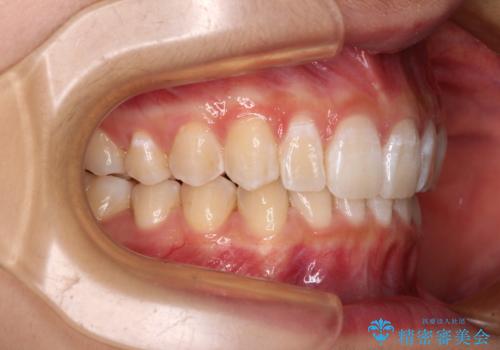

インビザラインをしっかりと装着したことはもちろん、高校生は歯の動きが早いため、非常に短期間で治療を終えることができました。

- 1年3ヶ月

- 5-10回